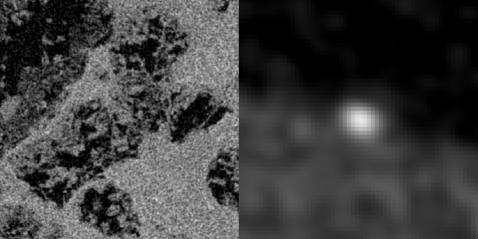

Gaussian-filtered FBP

ASD-POCS (0.1 mm pixels)

ASD-POCS (0.025 mm pixels)

We illustrate the problems with employing a matched-resolution grid, 10241024, and a very high resolution grid, 40964096, with the basic ASD-POCS algorithm. The pixel width is 0.1 mm for the former grid and 0.025 mm for the latter. Note that the rabbit support projects onto the middle 1000 bins of the full projection. The FBP image is shown on a 40964096 grid, but because FBP is based on an explicit inverse its pixel values are not affected by the grid size. In Fig. 2 the matched grid clearly leads to a loss of resolution relative to FBP, because the image is forced to be uniform over the 0.1mm 0.1mm squares. Simply going to a larger array does improve the ASD-POCS image, but the noise pattern shows additional false structure when compared with the FBP image. These structures arise from the fact that the imaging problem is under-sampled by roughly a factor of ten and this under-sampling occurs in both view-angle and detector-bin directions. The random, sparse specks that appear could be confused with micro-calcifications in the context of breast imaging.